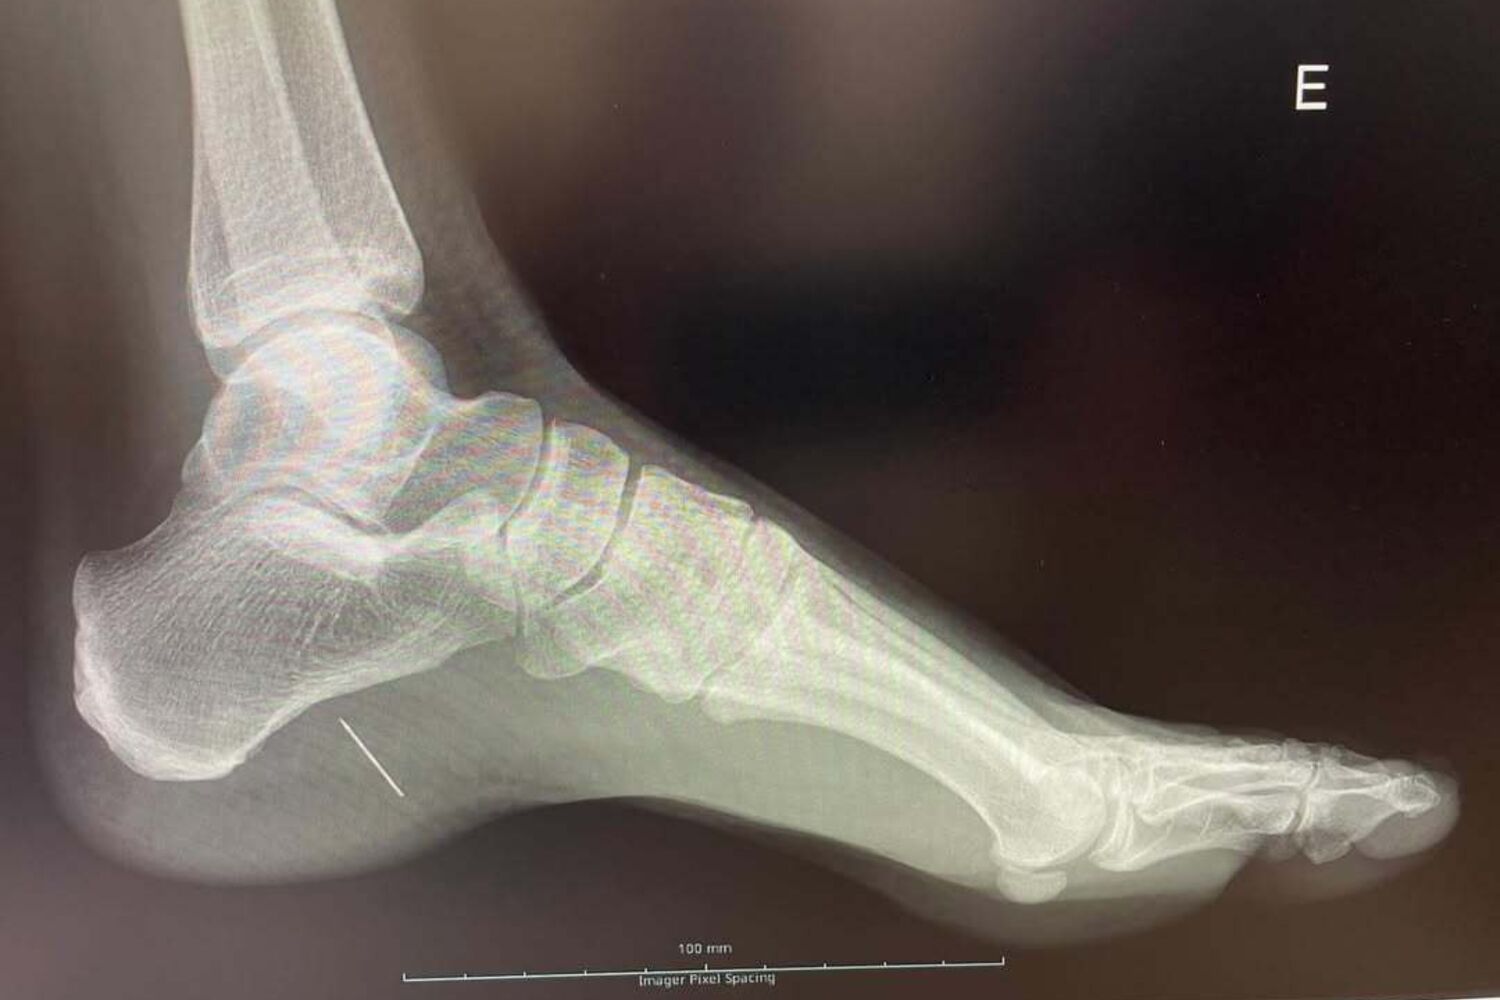

"Piquei-me no pé com um alfinete. Doeu, continuei com a minha vida mas a dor não passava. Andei de muletas sempre a achar que acordaria melhor no dia seguinte… Até que ao 7.º dia fui fazer um raio X", começou por contar a designer de vestidos de noiva no Instagram.

"Algo não estava bem. Não tinha o pé inchado, não tinha febre, não estava infetado, nem vermelho nem quente mas tinha um alfinete lá dentro! O filho da mãe ainda deu luta ao cirurgião, partiu-se mas lá saiu… Esta brincadeira deu direito a uma cirurgia em bloco operatório, anestesia geral e uma semana de repouso! NUNCA MAIS ANDO DESCALÇA", escreveu ainda, uma mensagem que valeu um recado da irmã Matilde Breyner.